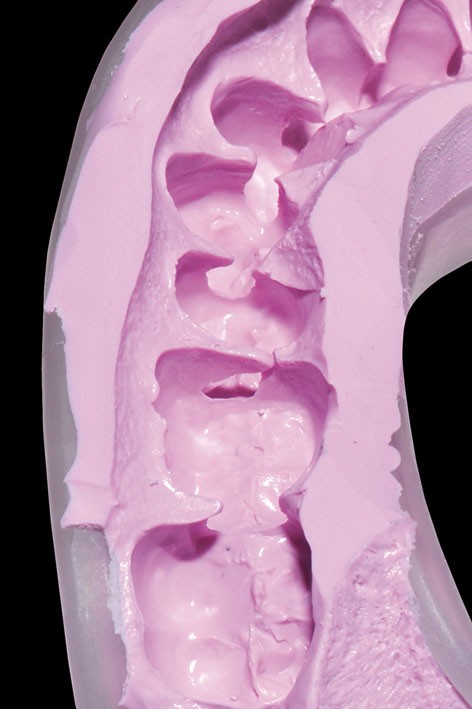

2. Une empreinte mandibulaire est réalisée à l’aide de 3M™ Imprint™ 4 Penta™ Preliminary pour obtenir une gouttière qui servira à la réalisation de la future prothèse transitoire.